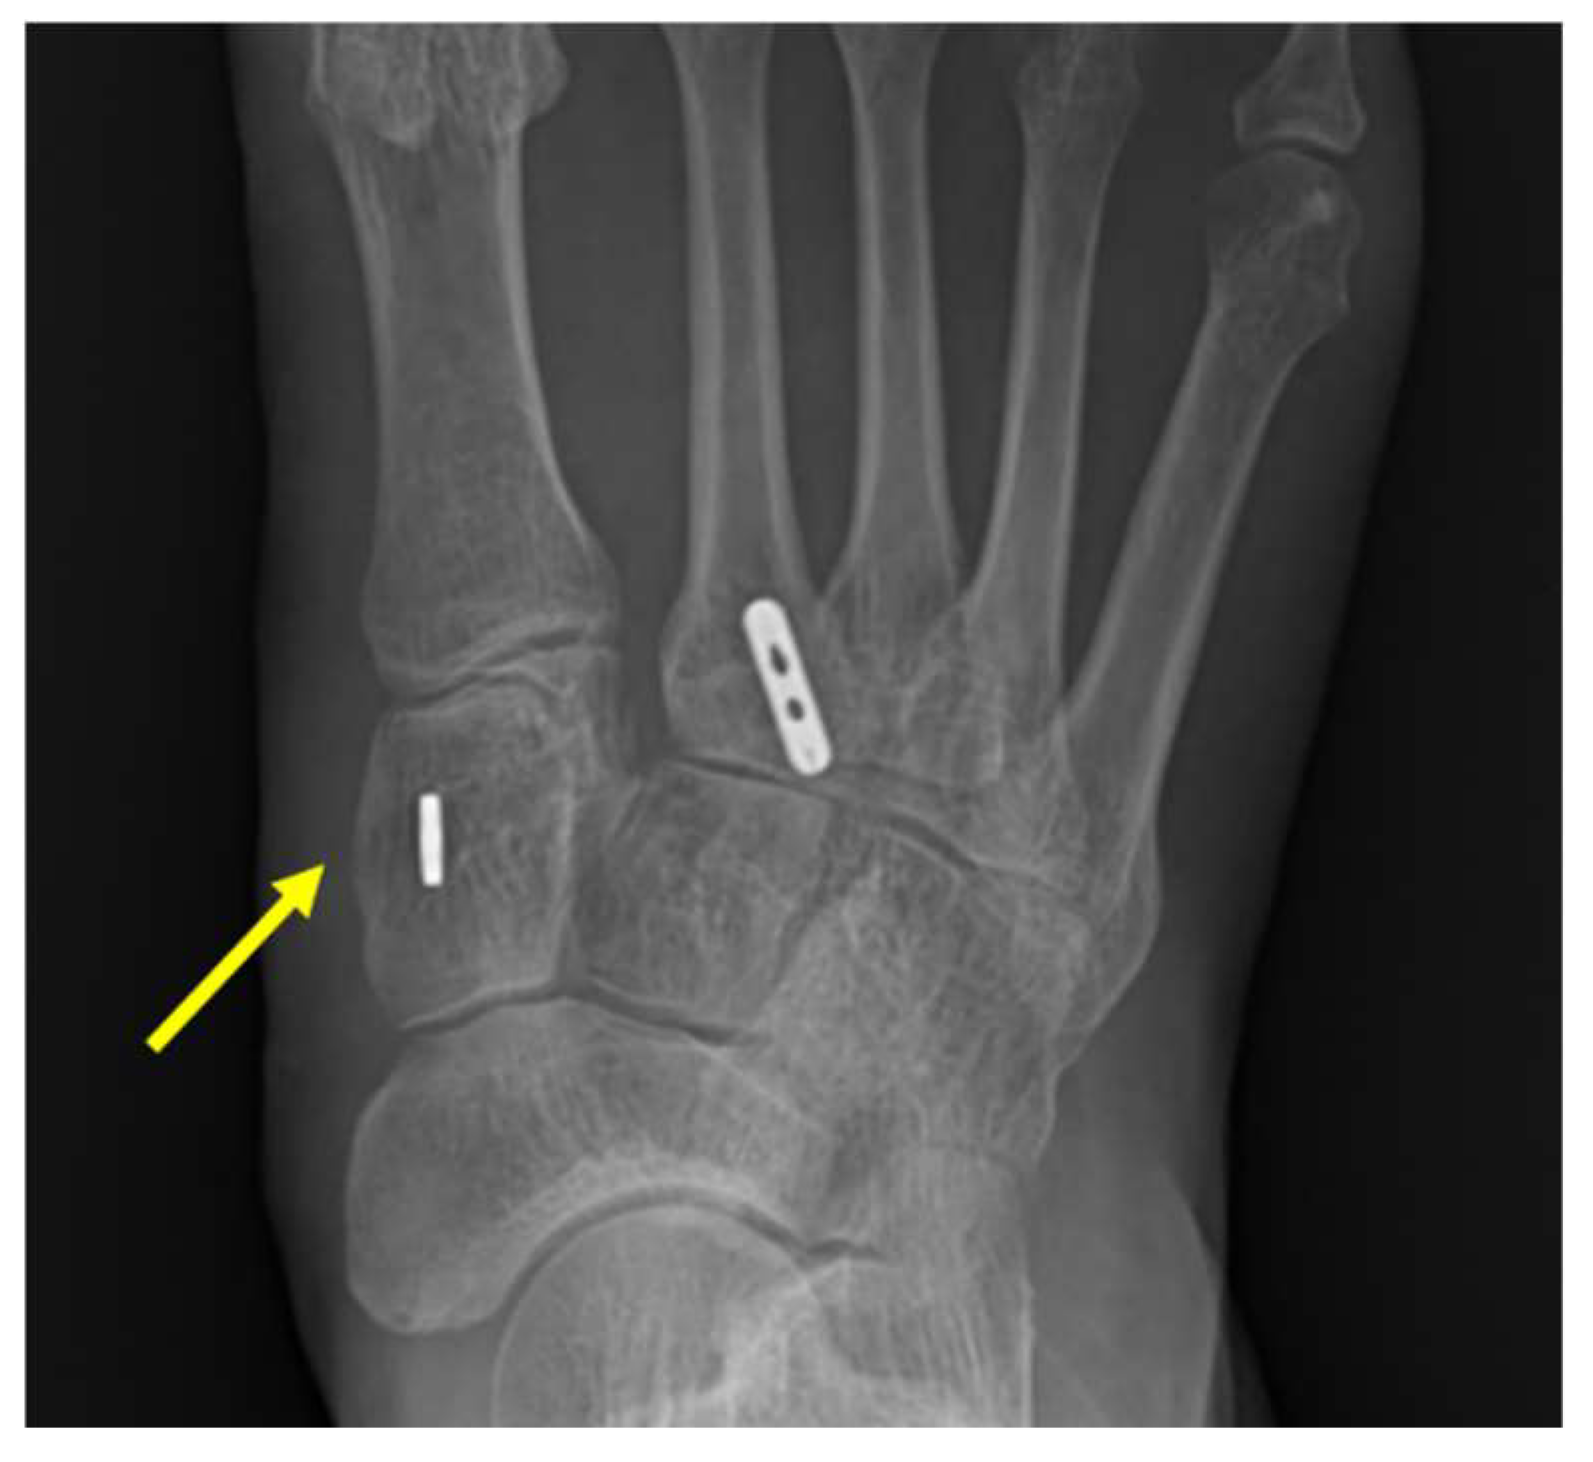

Only around 0.20% of all orthopedic injuries are Lisfranc joint injuries, which are an exceptionally uncommon trauma [1]. The severity of the injury is typically described as ranging from a little nondisplaced sprain to an apparent fracture dislocation of the midfoot. Ligamentous Lisfranc injury is typically produced by low energy trauma, making it challenging to identify and treat, in contrast to Lisfranc joint fracture-dislocation, which is typically caused by high energy trauma. If not properly and promptly treated, it may result in instability and post-traumatic arthritis in the patient [2]. Unfortunately, the prevalence of ligamentous Lisfranc injuries is rising as sports and professional athletes become more and more prominent (Figure 1). Numerous activities, including football, gymnastics, horseback riding, and jogging, have been linked to ligamentous Lisfranc injuries [3,4]. However, unlike high intensity injuries, indicators of ligamentous Lisfranc damage might not be as visible. The actual frequency of these injuries may thus be overestimated. Therefore, to diagnose ligamentous Lisfranc injuries, a proper physical examination and radiographs are needed.

Figure 1. Standing plain radiographic image of bilateral foot. Diastasis between medial cuneiform and 2nd metatarsal base is observed on left foot (yellow arrow).

After low intensity trauma, any patient who complains of midfoot discomfort should be examined, and Lisfranc damage should be ruled out. The injury mechanism is known to entail an axial stress applied to the forefoot being forcedly abducted or the foot being in a plantar flexed posture [5]. Physical findings that are favorable may include midfoot edema, plantar ecchymosis, difficulty bearing weight, a positive piano key stress test, and the dorsal drawer test of the medial column. Diastasis of the intermetatarsal gap between the first and second metatarsals, enlargement of the space between the medial cuneiform and second metatarsal base, the presence of a second metatarsal base fleck, and dorsal subluxation of the metatarsal base on a lateral view are all significant radiographic findings [6]. Patients with a strong clinical suspicion of Lisfranc injury and ambiguous radiographic results may undergo computerized tomography (CT) or magnetic resonance imaging (MRI).